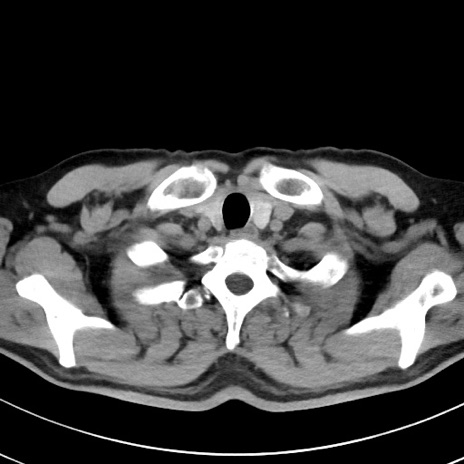

【腹部TIPS】症例29 参考症例 CT(横断像)

症例

70歳代男性